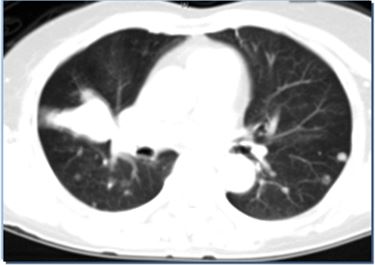

Hình ảnh CT ngực trước và sau điều trị

Trước điều trị                                 Sau 10 tháng

Trước điều trị: Hình ảnh u phân thùy giữa phổi phải. Kích thước 3 x 4 cm. Có nhiều nốt di căn ở cả hai bên phổi.

Sau điều trị: Đáp ứng gần hoàn toàn, u nhỏ đi nhiều và số lượng các ổ di căn hai bên phổi giảm nhiều.